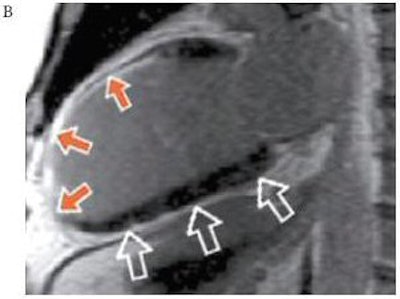

| Patient who sustained an anterior myocardial infarction. A Top (above): Apical two-chamber view on MCE after contrast agent injection (SonoVue, Bracco, Milan, Italy) with absence of contrast opacification (solid arrows) at the apex and anterior wall, which were akinetic. The normal, remote segments (outlined arrows) show normal contrast intensity. A Bottom: Replenishment curves in the akinetic segment (yellow) demonstrate very low microbubble velocity and myocardial blood flow remote, normal segment (red). B (below): The corresponding image on CMR demonstrates TEI > 75% in the akinetic segments compared to remote normal remote segment. Images courtesy of Bracco and Dr. Roxy Senior, Northwick Park Hospital, Harrow, U.K. |